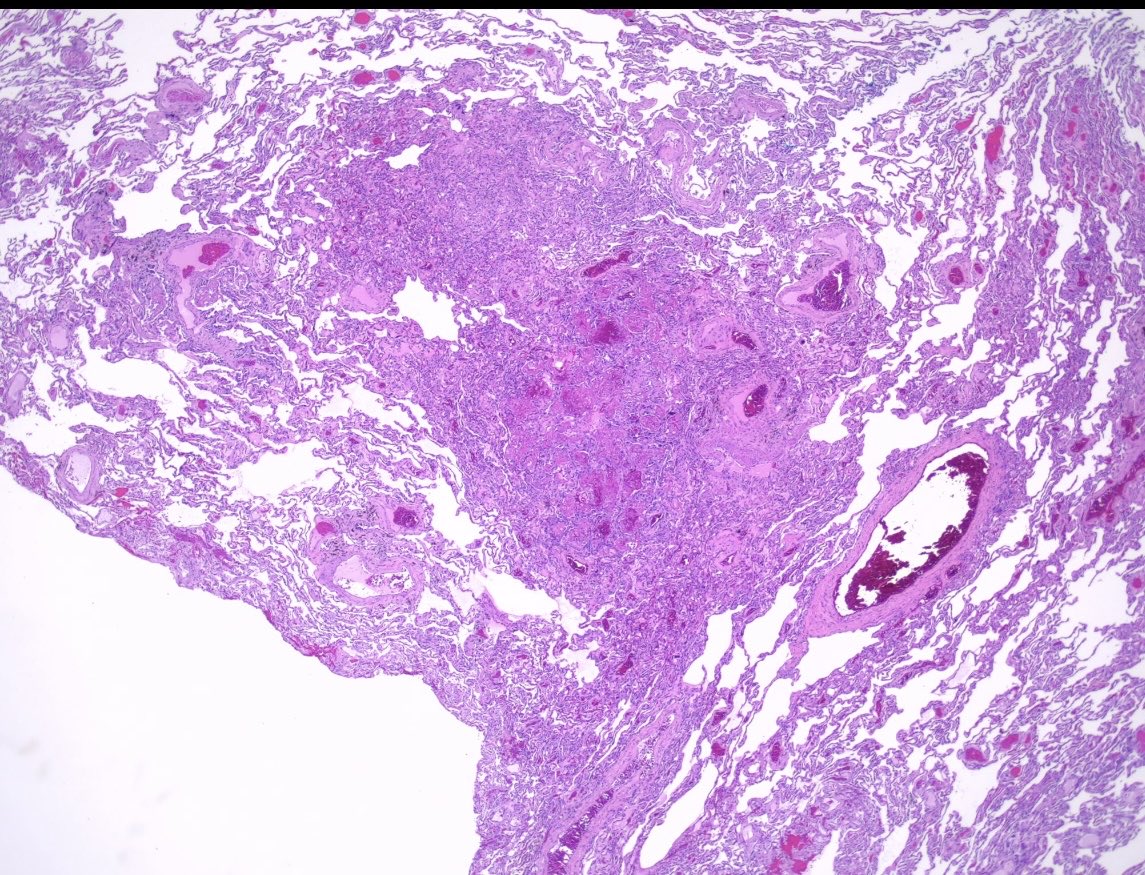

Radical orchidectomy Intratubular embryonal carcinoma with necrosis (in images) There was adjacent mixed germ cell tumour including embryonal carcinoma #PathTwitter #Pathology #PathResidents #GUPath

DrLaurenceGalea's tweet image. Radical orchidectomy

Intratubular embryonal carcinoma with necrosis (in images)

There was adjacent mixed germ cell tumour including embryonal carcinoma

#PathTwitter #Pathology #PathResidents #GUPath